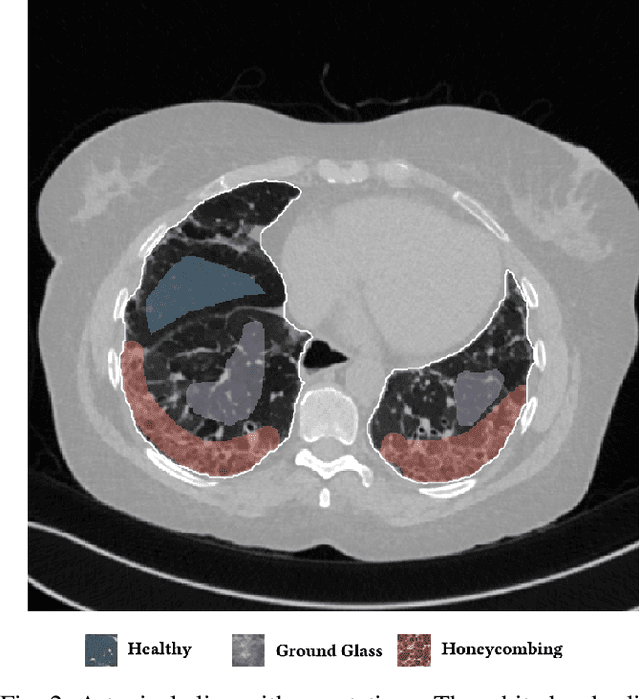

Abstract:Early and accurate diagnosis of interstitial lung diseases (ILDs) is crucial for making treatment decisions, but can be challenging even for experienced radiologists. The diagnostic procedure is based on the detection and recognition of the different ILD pathologies in thoracic CT scans, yet their manifestation often appears similar. In this study, we propose the use of a deep purely convolutional neural network for the semantic segmentation of ILD patterns, as the basic component of a computer aided diagnosis (CAD) system for ILDs. The proposed CNN, which consists of convolutional layers with dilated filters, takes as input a lung CT image of arbitrary size and outputs the corresponding label map. We trained and tested the network on a dataset of 172 sparsely annotated CT scans, within a cross-validation scheme. The training was performed in an end-to-end and semi-supervised fashion, utilizing both labeled and non-labeled image regions. The experimental results show significant performance improvement with respect to the state of the art.